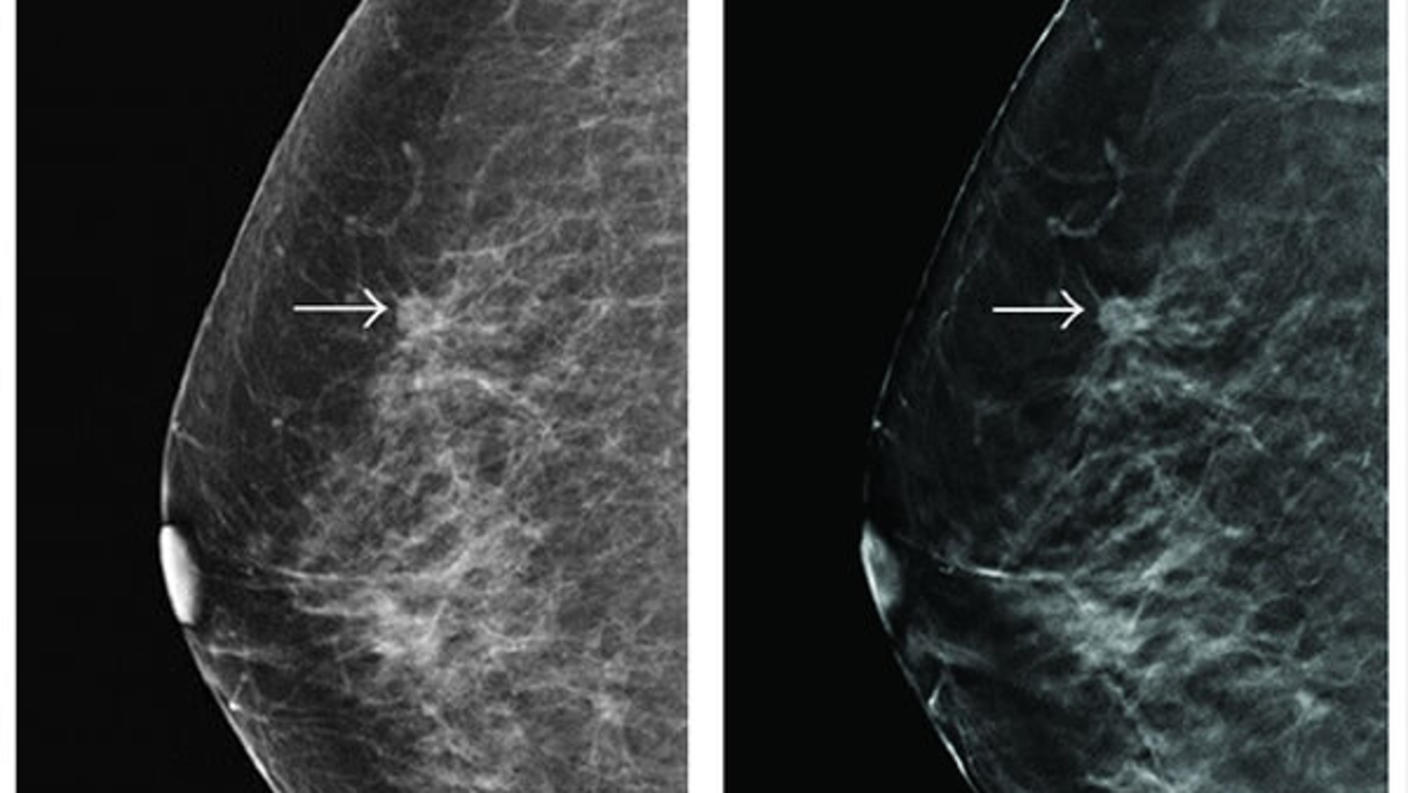

Cancer Screening and Early Detection Research

NCI supports a variety of programs designed to improve early detection and enhance cancer screening.

Cancer Diagnosis Research

NCI supports research on the development of tests and imaging technologies to improve the diagnosis of cancer.